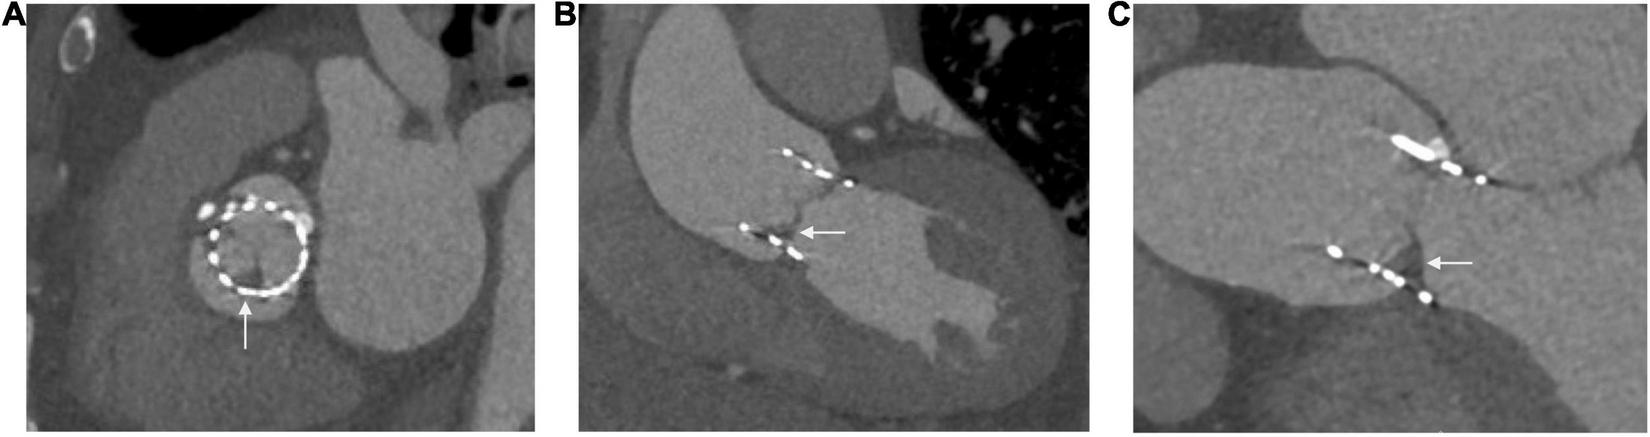

Multi-slice CT angiography has provided important insights into the natural history of prosthetic valves with a particular focus on valve thrombosis. Hypo-attenuated leaflet thickening (HALT) can be found in 10–38% of prosthetic valves (82, 83), with the prevalence possibly higher in TAVR valves (84). Although lacking histological confirmation, this is highly suspected to be thrombus, based on its resolution with anticoagulation (85). HALT usually involves the periphery and bases of a leaflet and extends to a varying degree toward the center of the bioprosthesis (Figure 4) (4). HALT can develop as early as 5 days post-TAVR and has been shown to either progress, stabilize or regress over time (82, 83). Progression of HALT can lead to valve dysfunction described as restricted leaflet motion. This causes an increase in echocardiographically defined transvalvular gradients and eventually leads to symptoms of valve dysfunction (83). CT provides a reliable and potentially more sensitive methodology compared to transthoracic echocardiography for identifying and monitoring HALT (86, 84). It can also help determine management; the composition of acute thrombus has a low attenuation <90 HU, whereas chronic thrombus has values of 90–145 HU. Small acute thrombi are amenable to thrombolysis making this differentiation between types of thrombi important (87). 2D MPR provides an axial cross-sectional assessment to identify leaflet abnormalities. 3D volume rendered CT acquired through multiple phases provides confirmation of the leaflet abnormalities. When reconstructed into a movie (4D virtual reality CT), this can reliably illustrate restricted leaflet motion (4, 88, 89). Prophylaxis and treatment of thromboembolic disease associated with prosthetic valves have important implications for anti-thrombotic therapy, which is discussed elsewhere (90).

FIGURE 4

Hypo-attenuated leaflet thickening seen in three views of the same patient (A) at the level of the sinus of Valsalva, (B) left ventricular outflow tract view, (C) three chamber view.